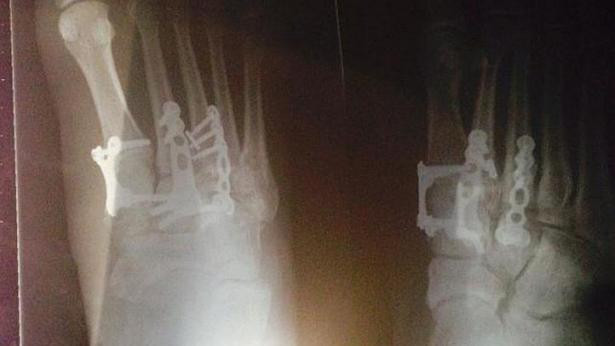

| Tình trạng thương tật của cô Erin Croker |

Sau đó, một tiếp viên hàng không cũng mất thăng bằng và ngã lên người cô, dẫm lên chân phải của Erin khiến cô bị thương nặng phải phẫu thuật. Sau cú dẫm chân đó, Eric bị gãy nhiều xương, vết thương sâu làm rách dây chằng khiến cô không thể đi làm trong vài tuần.